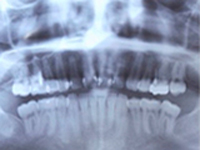

歯周病は1本の歯だけではなく、お口の中にある全ての歯を支えている歯周組織を破壊していく病気です。まずレントゲン撮影をし、歯槽骨(歯を支える顎の骨)が現在どの程度失われているか確認します。それから、歯周ポケットを測定し、歯周病の進行程度を全ての歯について調べていきます。